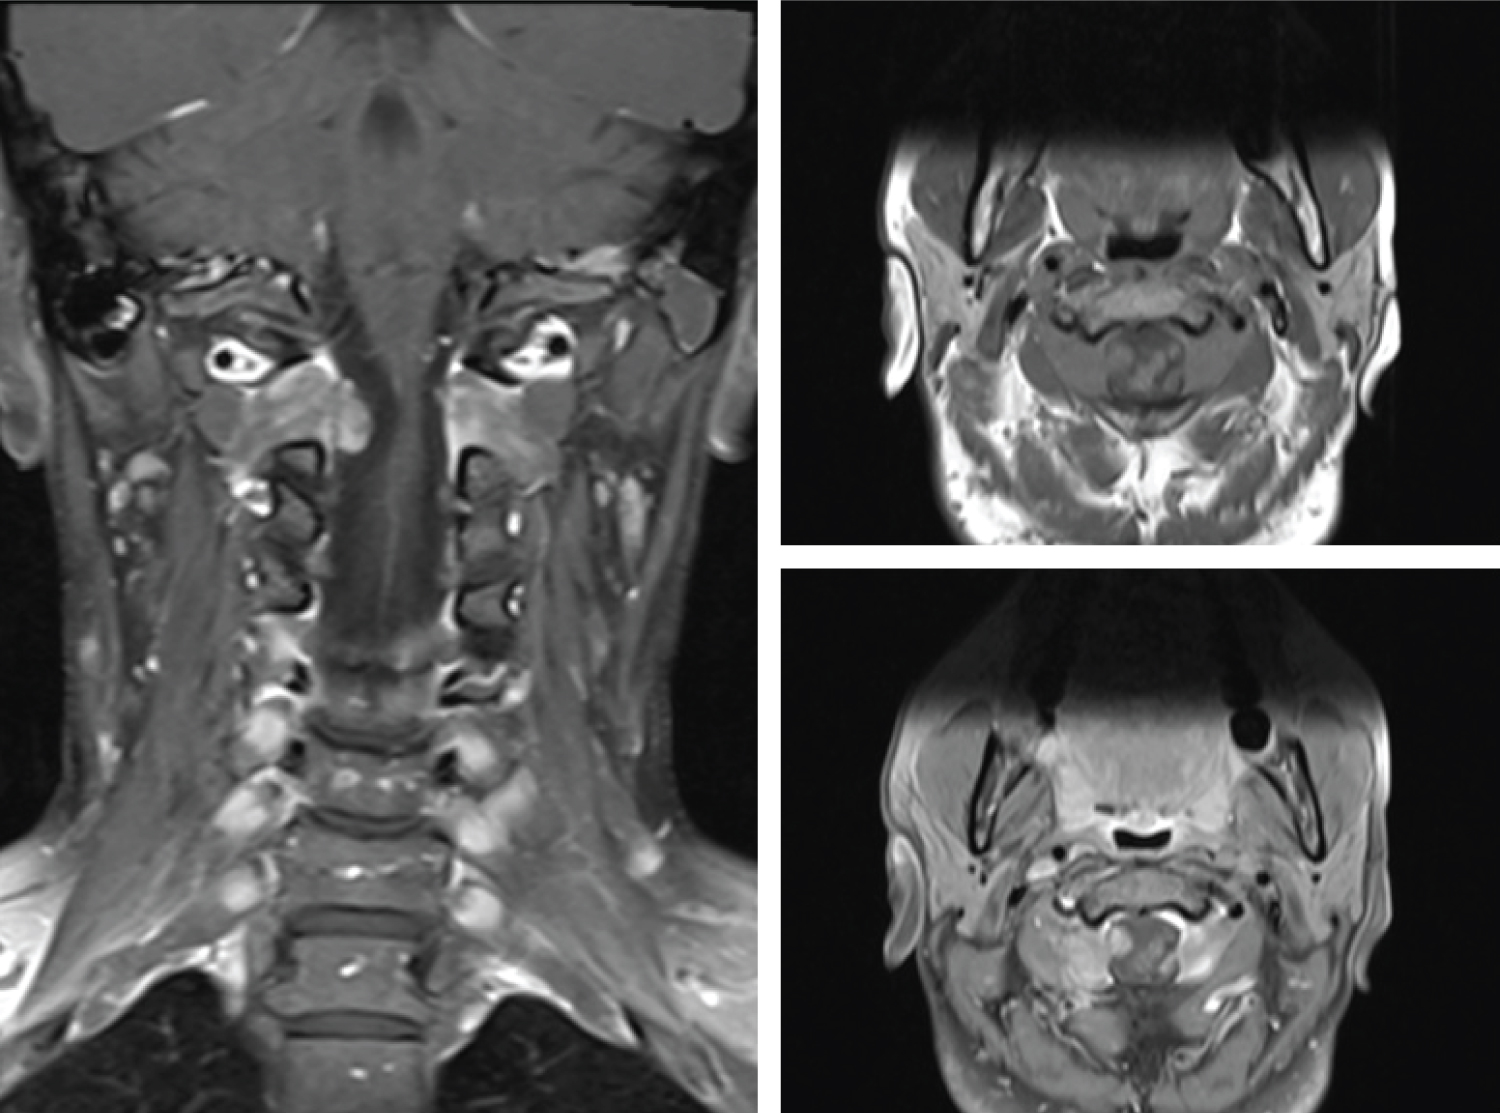

MRI of the brain and cervical spine was ordered, and it revealed enlarged dorsal root ganglia bilaterally at C2, C3 and C4 nerves. These were most prominent at C2 nerve roots bilaterally, with medial and anterior enlargement that extended intradurally and compressed the cervical spinal cord (Figure 1). Hyperintense signal on T2 sequences were noted on the cord at this level, consistent with myelomalacia. MRI of the brain was within normal limits. The patient consented to posterior C1-2 decompression and excision of the C2 nerve root tumours, with the possibility of C1-2 fusion if instability was created.

Figure 1: Left image - pre-operative coronal T1 post-contrast MRI showing bilateral dumbbell C2 tumour with intradural extension and cord compression.

Right image - pre-operative axial T1 MRI pre-contrast (top) and post-contrast (bottom) showing C2 ganglioneuroma with mild contrast enhancement and intradural extension. View Figure 1